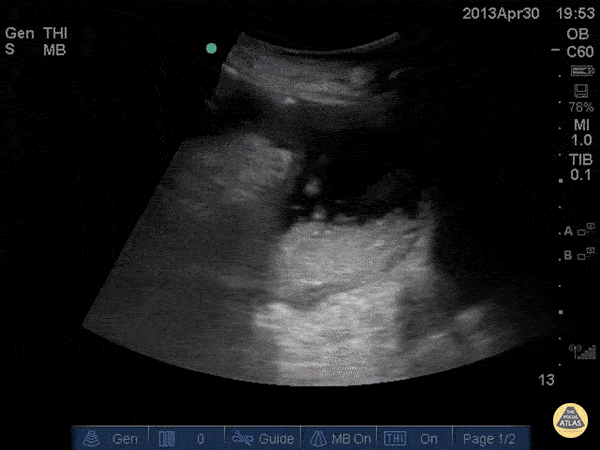

Bowel-GI - Iguapoo Falls

Small bowel obstruction with a steep precipice and tumbling feces. We call this Iguapoo falls. Andrew Liteplo MD, RDMS - Massachusetts General Hospital Chief, Division of Ultrasound in Emergency Medicine Director, Emergency Ultrasound Fellowship